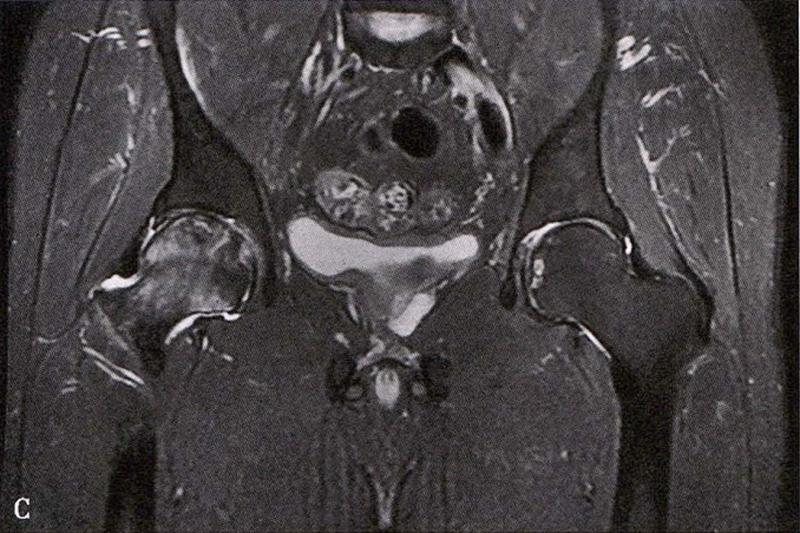

(2)MRI检查

MRI检查是早期诊断股骨头坏死最具特异性、灵敏度的检查方法。当怀疑有股骨头坏死,而X线片无明显异常时,应行MRI检查。诊断时可根据髋关节X线、MRI显示的坏死面积和塌陷程度进行ARCO分期。

冠状面及横断面MRI图像

MRI示双侧股骨头坏死,冠状面显示右侧股骨头坏死(图A、C),横断面显示双侧股骨头坏死(图B、D);T1加权像(图A、B)显示硬化带为低信号,T2加权像(图C、D)显示右侧骨坏死硬化带外围高信号的骨髓水肿,左侧无骨髓水肿。